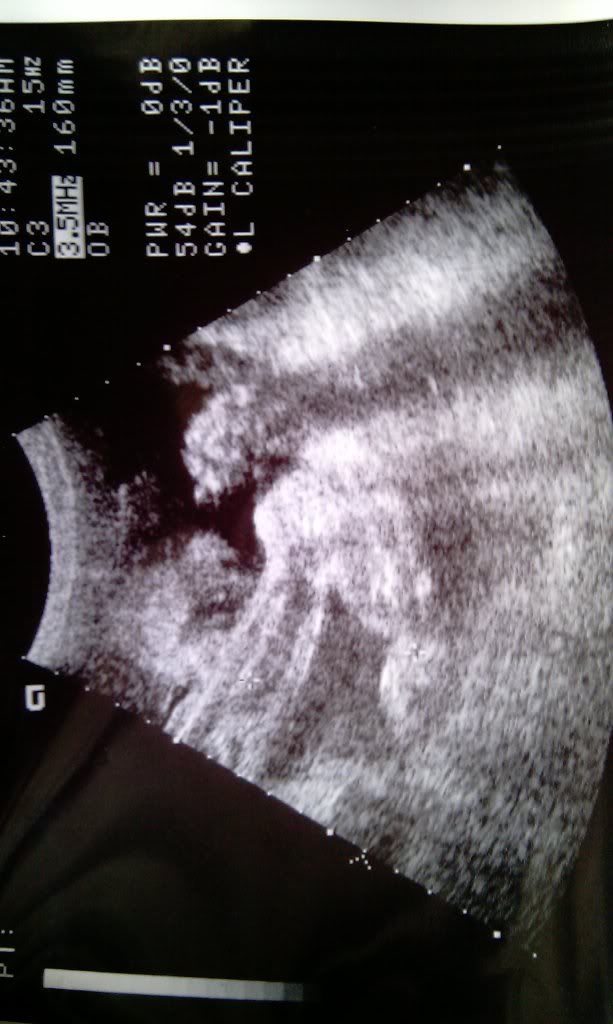

From community.babycenter.com

What does a cleft lip look like on ultrasound? BabyCenter What Does A Cleft Palate Look Like On Ultrasound the nyberg 1995 antenatal ultrasound classification system is one that correlates very well with the severity of the defect with outcomes and. Submucous clefts are those defects of the hard and soft palate where a mucosal. cleft lip and palate fetus with mouth open demonstrates a defect which is part of the open mouth. Cleft lip and cleft. What Does A Cleft Palate Look Like On Ultrasound.